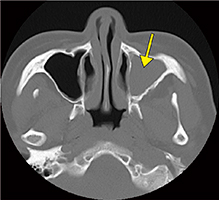

また、Aquilion Lightning/Helios Editionには、金属アーチファクト低減技術の“SEMAR”が標準搭載されている。SEMARの適用について長野技師は、「撮影後でも必要があれば後から処理ができるので便利です。腹痛を訴えて受診された患者さんで、腹部に滞留した金属製の義歯の状態がSEMARで明瞭に描出できたという症例(図3)を経験しました。アーチファクトの低減効果を実感しています」と述べる。

■Aquilion Lightning/Helios Editionによる臨床画像

図3 SEMAR適用症例

金属製の義歯を飲み込み腹痛を訴えた患者の腹部CTで、SEMARを適用し正確な治療計画を立てることができた。

a:SEMAR適用なし b:SEMAR適用あり